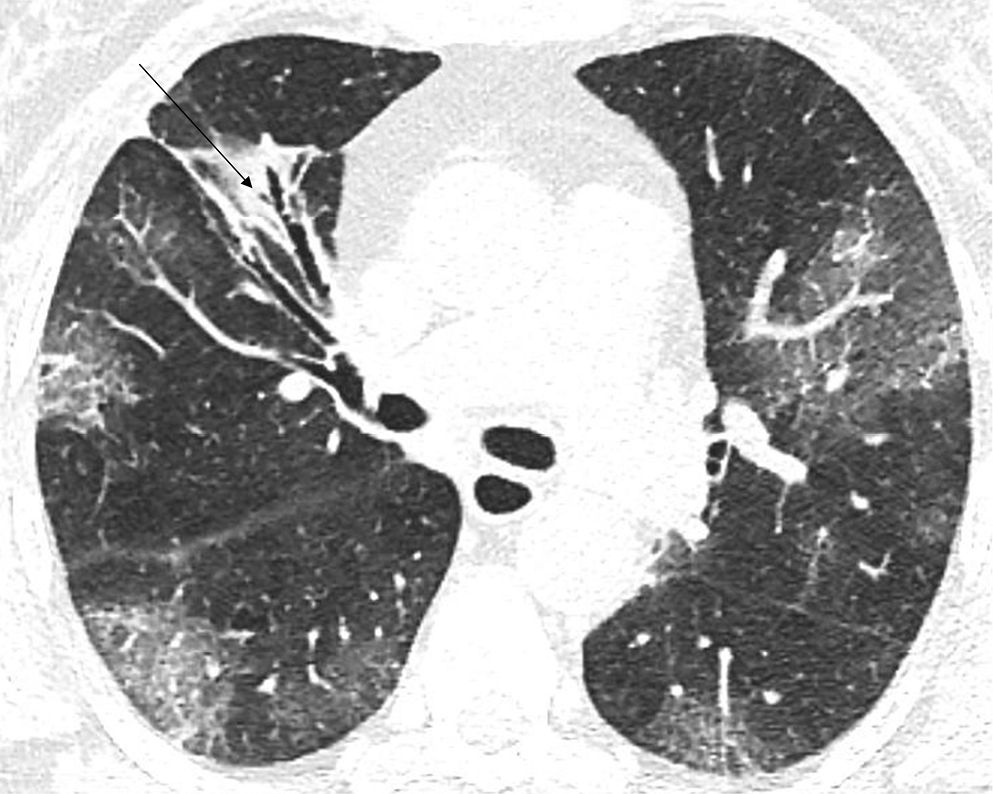

In the early stage of COVID-19, the primary CT findings observed are bilateral GGOs with a mostly peripheral and subpleural location. Ground-glass opacity is a term used to describe hazy areas with the preservation of vascular and bronchial margins which are a result of the partial filling of air spaces, intestinal thickening, or the coexistence of both (Figure 2).10 Another phenomenon is described as having ‘crazy-paving’ appearance. This is a combination of GGO and interlobular or intralobular septal thickening (Figure 3). This condition is mostly present in severe cases of COVID-19 pneumonia. Consolidations (multifocal, patchy or segmental) are another sign of COVID-19 progression (Figure 4).11 Several days after developing the first symptoms, chest CT can reveal linear consolidations and reversed halo signs in the patient’s lungs.12 Radiographic features typically include bronchovascular thickening (Figure 5).13